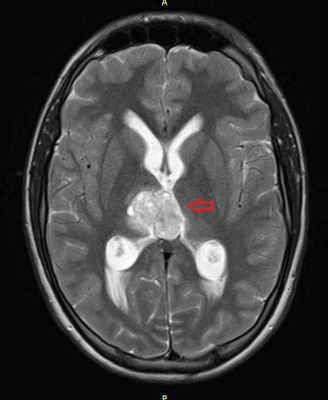

Рисунок 7. - Герминома головного мозга.

Герминомы формируют инфильтрирующие опухоли больших размеров, часто являющиеся источниками субарахноидальных (между мягкой и паутинной оболочками мозга) и вентрикулярных (желудочковых) метастаз.

Рисунок 9. - метастаз в головной мозг при герминогенной опухоли.